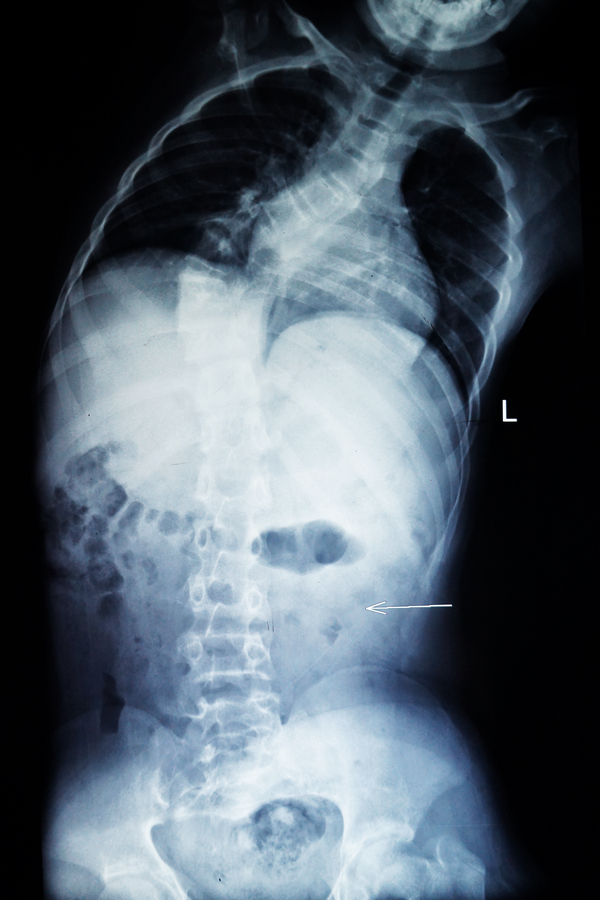

您的位置: 首页>科室导航>骨科>脊柱外科二区>科室新闻